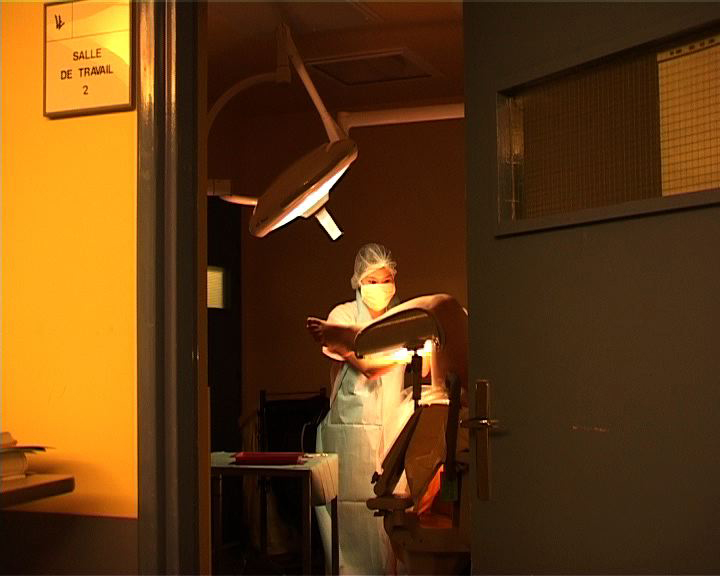

Que se passe-t-il derrière ces portes, ces couloirs d'hôpital aux couleurs saturées ? Qu'éprouve-t-on à cet endroit, avec ces jeunes femmes en tenue rose passé, dans le battement et le souffle des machines, la douleur ? Parmi les tuyaux, les poches, les lumières, les chiffres et les tracés des appareils et des alarmes ? Les cris, l’abstraction des vocables techniques, les tensions, les frottements, et la douceur aussi des gestes silencieux ? Quels interstices faut-il regarder pour assister à une cérémonie secrète faite de douleur, d'efforts, de concentration, de rythmes qui s'accélèrent, de voix qui encouragent, et où la délivrance ne va pas sans le regard d’adieu minutieux à ce qu'on doit laisser ?

Née en 1976 à Paris, Pauline Higgins suit le double chemin de l'ethno-anthropologie et de la maïeutique (sage-femme). Ces deux désirs sont nés au Sénégal avant d'être enrichis par l'EHESS et son étude de terrain "Une maternité de brousse en plein Paris" qui montre que l'ignorance des marquages rituels peut, avec réserve, faire place à l'altérité. Pauline travaille sur le toucher, le tact, le "care", l'attention, l'intime. "Passage", réalisé avec les Ateliers Varan, interroge la technologie entourant l’accouchement. "Vagues", conçu avec la Fémis, est un essai sur la mémoire généalogique. Dans les mangroves du Siné-Saloun, elle précise son intérêt pour les systèmes de guérissage, et l’intentionnalité des gestes. "Naître vient de nature", adressé à l’équipe de Bruno Latour qu'elle rejoint, questionne la "culture de la nature" chez les sages-femmes. "Toucher c'est voir", filmé avec pudeur, fait entendre leurs gestes et leurs intentions. "R6/2 ou comment faire connaissance avec les animaux d'expérimentation", performance collective, veut donner un nom à ces non-humains, invisibles médiateurs sacrifiés. Pauline expérimente les périodes liminales, floues, entre nature et culture. Son projet de film actuel interroge l’"être près", l’ombre, l’obscurcissement, l’obfuscation.